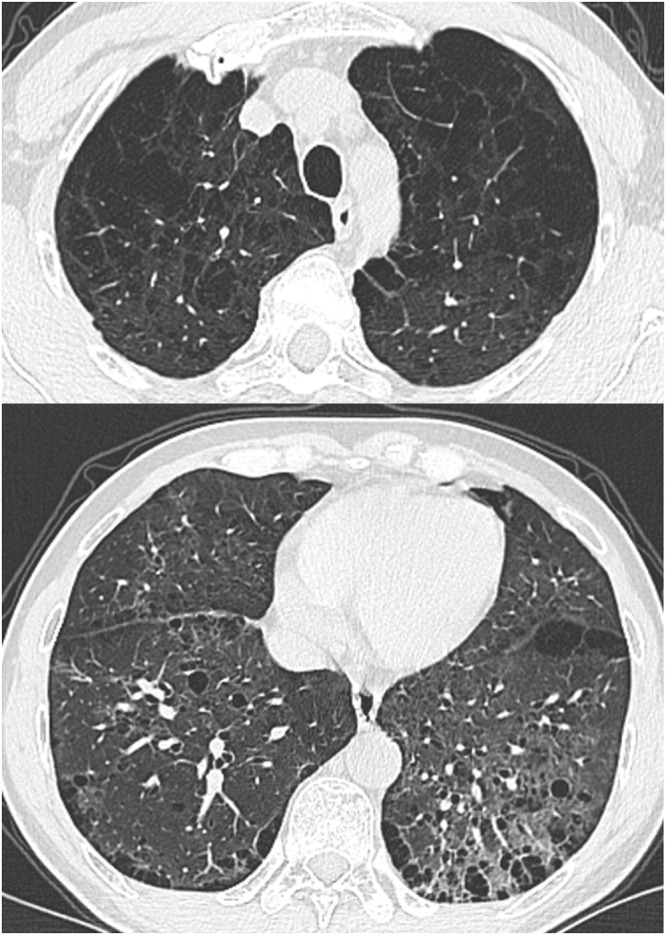

Emphysema is common in fibrotic interstitial lung diseases, and its combination with pulmonary fibrosis is known as "Combined Pulmonary Fibrosis and Emphysema (CPFE) syndrome". The diagnosis of CPFE significantly impacts treatment strategies and prognosis. In this article, we report the clinical, imaging, and especially the pathological features of two CPFE patients. Case 1: A 51-year-old male patient with a history of smoking. CT scans revealed interstitial lung disease combined with pulmonary bullae. Pathology showed extensive deposition of mononuclear cells in the alveolar spaces, with some cells phagocytosing pigment. Mild fibrous tissue hyperplasia was present in the lung interstitium, along with chronic inflammation and lymphoid nodule formation. The histological findings were consistent with desquamative interstitial pneumonia (DIP), and the clinical, imaging, and pathological correlation confirmed a diagnosis of CPFE. Case 2: A 58-year-old male, a driver with a history of dust exposure and smoking, was admitted due to chest tightness and a cough for 2 years. Chest CT revealed interstitial changes, emphysema, and bullae in both lungs. Histopathology showed fibrous widening of alveolar septa, mild chronic inflammation, and dust cell deposition, along with emphysematous changes and bulla formation, consistent with CPFE. The purpose of this report is to increase pathologists' awareness of this complex disease and emphasize the importance of multidisciplinary cooperation in the diagnosis and treatment of CPFE. Furthermore, this article encourages further research into CPFE.